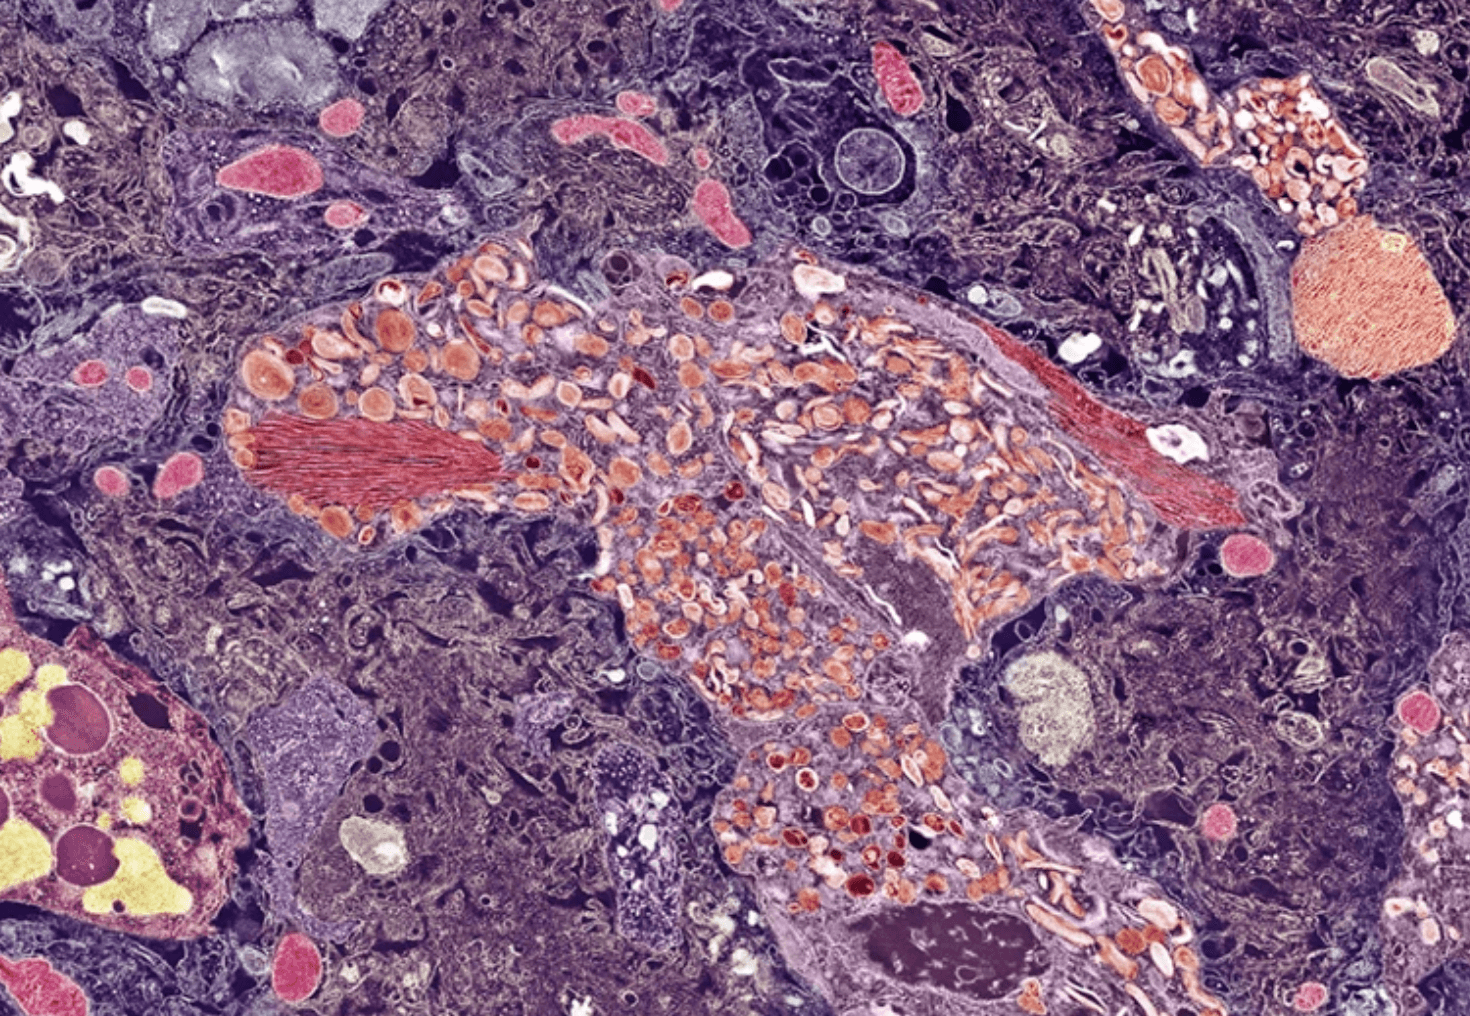

Choroba Alzheimera jest chorobą zwyrodnieniową mózgu, która cechuje się zaburzeniami pamięci oraz zachowaniami, które z czasem uniemożliwiają prawidłowe funkcjonowanie w codziennym życiu na jakimkolwiek poziomie. Podczas choroby w mózgu odkładają się białka o patologicznej strukturze, znane jako blaszki amyloidowe i białka tau, co powoduje stopniowe obumieranie neuronów. Im mniej komórek nerwowych, tym mniej przekaźników, które są niezbędne do prawidłowej pracy mózgu.

Prof. Lopera przebadał genomy i historie medyczne 1200 Kolumbijczyków, u których mutacja ta wystąpiła. Namierzono jednego mężczyznę z drugą mutacją, która sprawiła, że w wielu 67 lat miał jedynie łagodne zaburzenia poznawcze, podczas gdy “powinien” być ciężko chory. Kiedy przebadano jego mózg, okazało się, że jest w nim wysokie stężenie blaszek amyloidowych i białka tau. Mózg mężczyzny wyglądał jak mózg osoby z ciężką postacią demencji, ale nie cały. Jeden region, znany jako kora śródwęchowa (koordynująca pamięć i nawigację) miał niski poziom białek tau. Jak to możliwe?

Okazało się, że u mężczyzny wystąpiła mutację genu kodującego białko znane jako reelina, które wiąże się z zaburzeniami psychicznymi, m.in. schizofrenią. Niewiele wiadomo natomiast na temat roli reeliny w chorobie Alzheimera. Naukowcy przeprowadzili badania na genetycznie zmodyfikowanych myszach z tą samą mutacją i wykazali, że faktycznie wywołuje ona modyfikację białka tau – nie przyczepia się ono tak łatwo do neuronów. Podkreśla to rolę białka tau w rozwoju choroby Alzheimera i wskazuje, że nie wystarczy zniwelować blaszki amyloidowej, by objawy u pacjenta minęły. To by wyjaśniało, dlaczego istniejące leki usuwające amyloid beta z mózgu powodują jedynie łagodną poprawę.